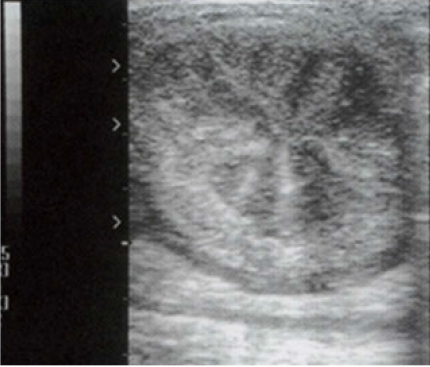

This ultrasound image shows a transverse view of a mare’s uterus taken as part of a pre-breeding

examination.

What is the correct description of the findings from this ultrasound?

There is uterine oedema present and the mare is in oestrus.